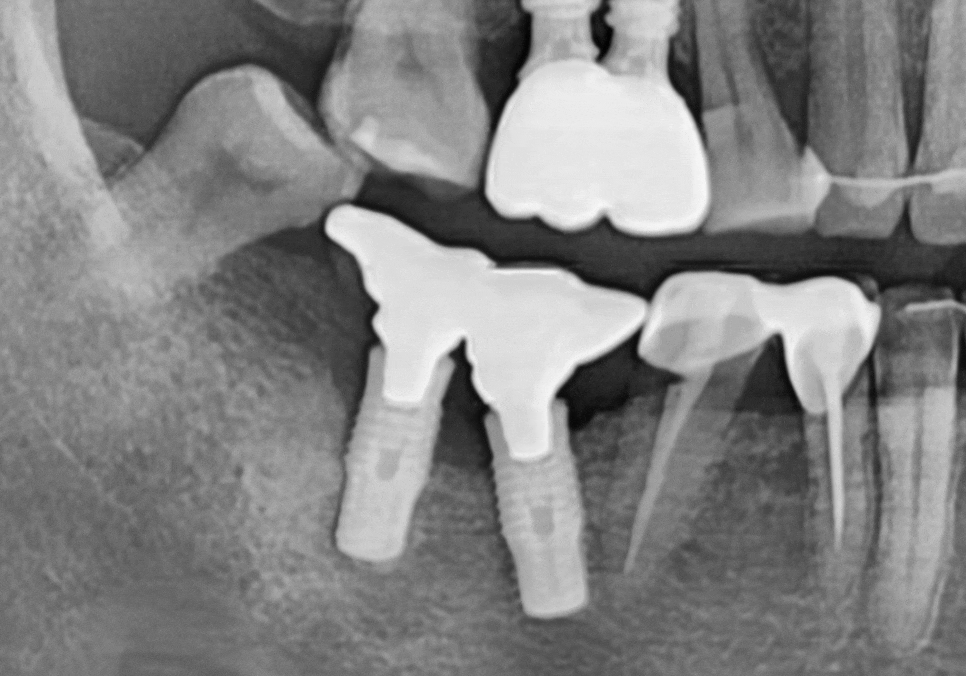

정밀 사진을 보니

어금니 쪽 임플란트(#46, 47) 주변 잇몸뼈가

염증(임플란트 주위염) 때문에

많이 녹아 있는 상태였는데요.

특히 CT로 분석해 보니 임플란트를

양옆에서 꽉 잡아줘야 할 뼈 중

한쪽 면이 염증으로 완전히 소실되어 있었죠.

임플란트 옆에 도자기로 씌워둔 치아(#45)의

보철물이 깨져 있었는데,

그 틈으로 음식물이 계속 끼어 들어가면서

치아 뿌리 깊숙이 충치가 생긴 상태였어요.